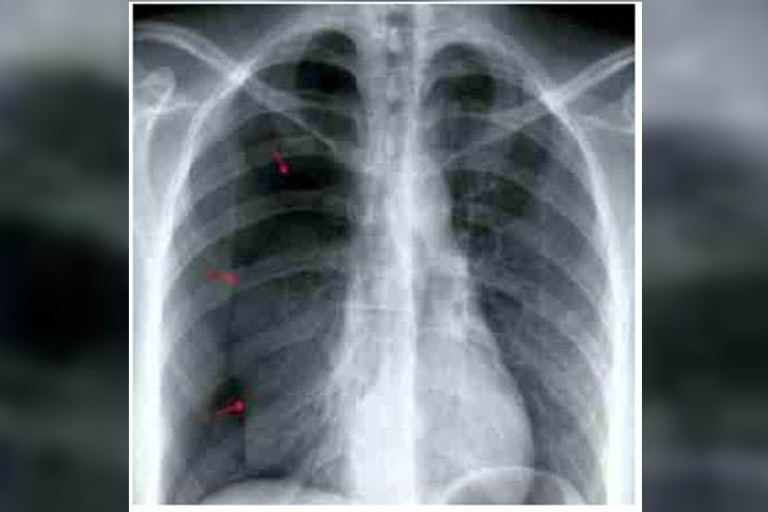

รอบนี้มาด้วยเหนื่อย+เจ็บอกขวาขึ้นมาทันทีทันใด ออกแรงหรือหายใจเข้าแล้วเจ็บมากขึ้น แพทย์ทำเอ็กซเรย์ดังภาพ พบปอดขวาแฟ่บลง (ลูกศรสีแดงคือแนวขอบของปอดที่หดลงมา)

บ่งบอกว่ามีภาวะปอดทะลุ (Pneumothorax) เกิดทางเชื่อมระหว่างโพรงอากาศในปอด กับช่องเยื่อหุ้มปอด (Pleural cavity) ลมได้เข้าไปยังช่องเยื่อหุ้มปอด ทำให้ปอดสูญเสียในการสร้างความดันในขยายปอด